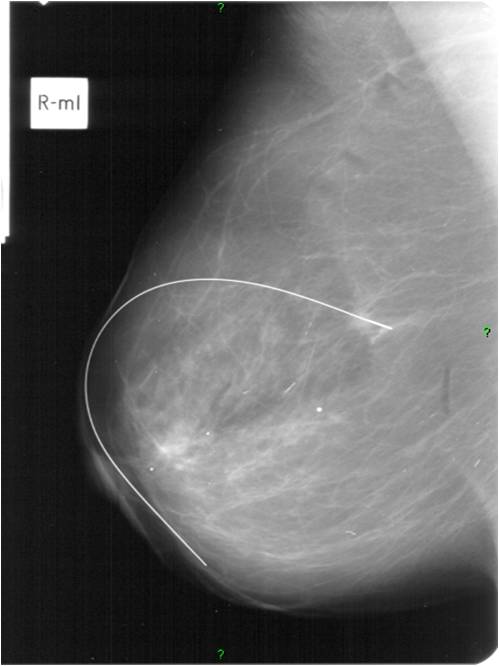

• Preoperative localization: (Picture 10.)

• Small, non-palpable tumor localization might be necessary in order to ensure optimal tissue excision.

• usually with a steel wire (hook wire or guide wire) localization. Guidance: US or X-ray.

• Localization confirmation can be performed with: specimen mammography (=mammogram taken of the removed breast part) (Picture11.)